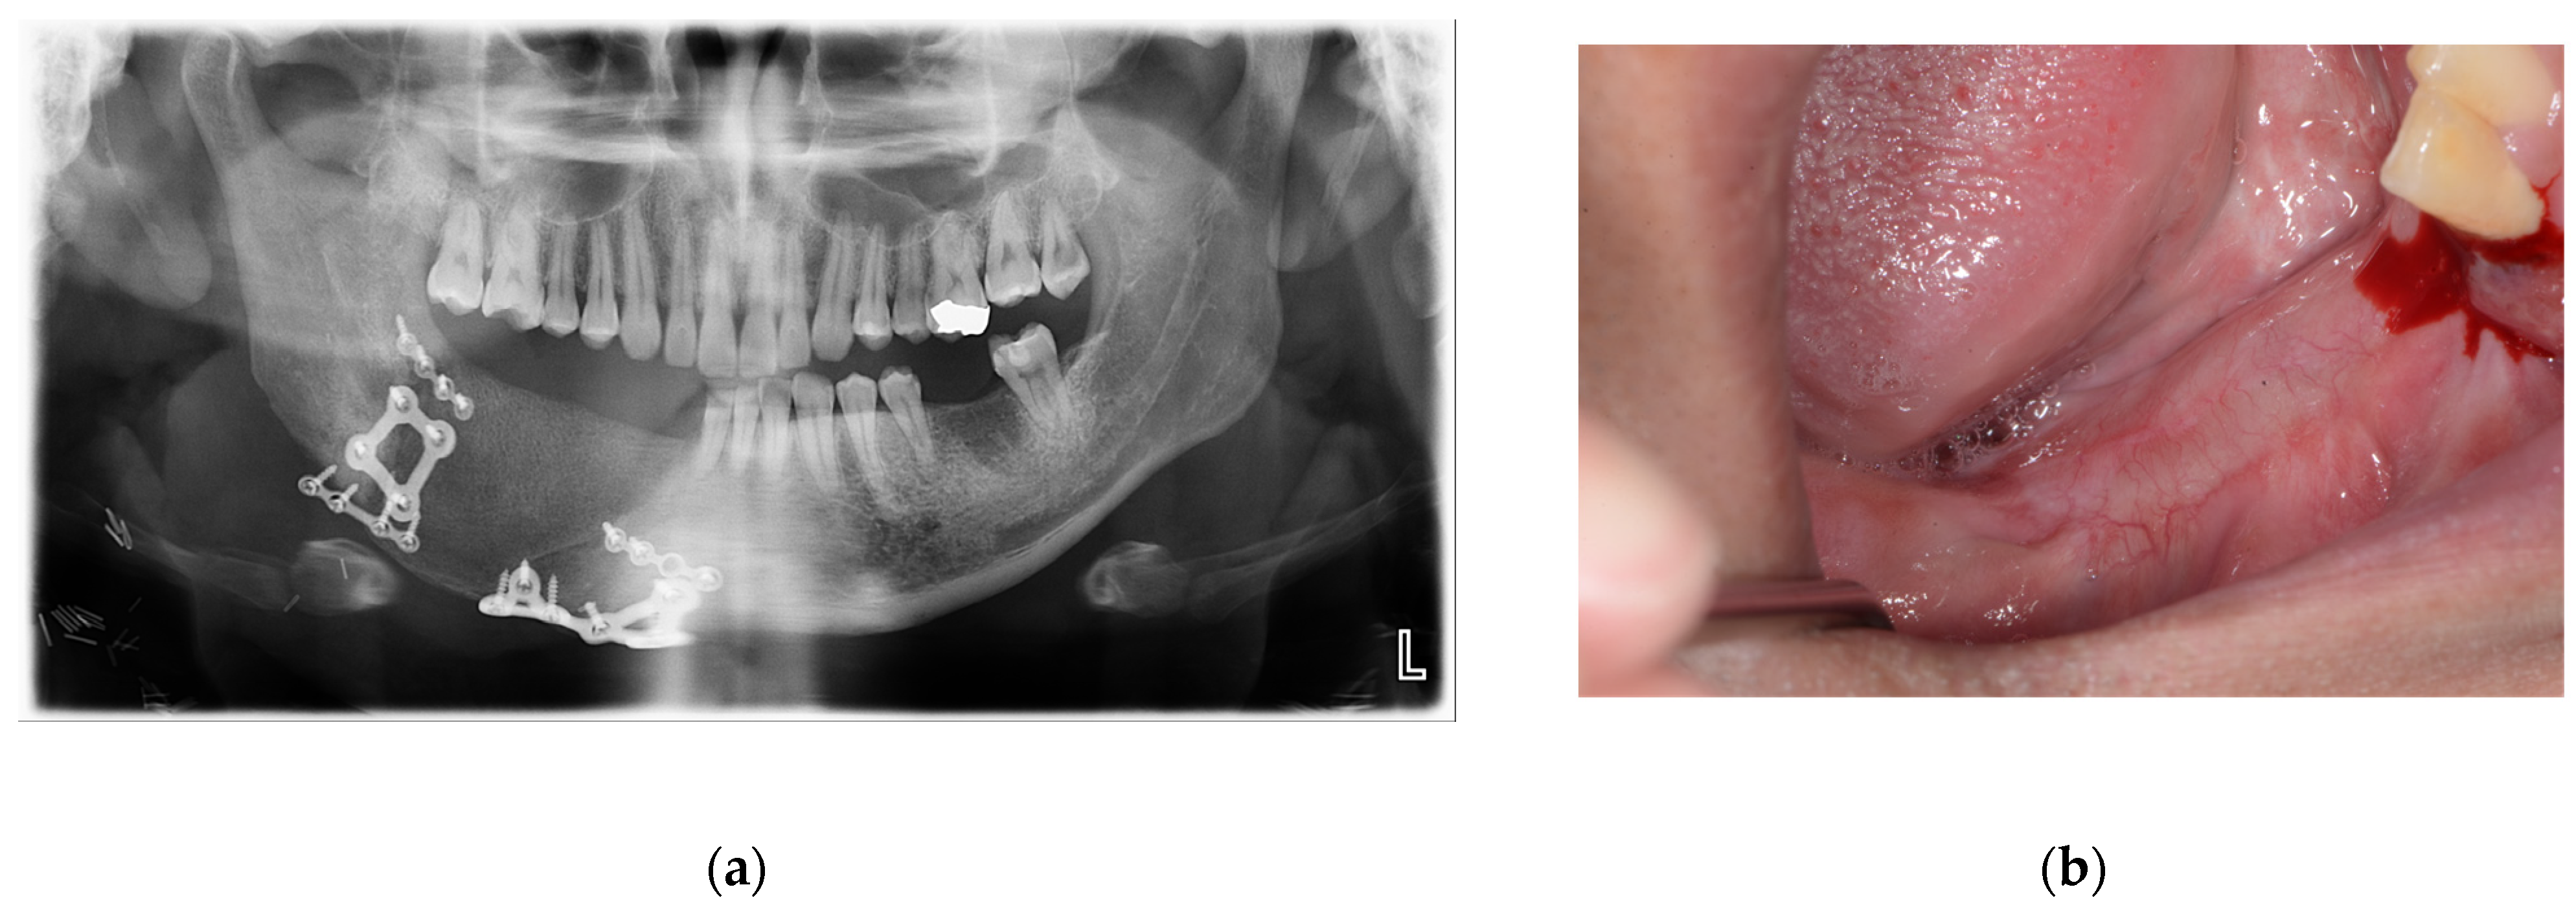

An accuracy analysis was performed using postoperative CT scans (Figure 6). Reconstruction of the mandible was successful, and no unusual findings were observed during the 6-month follow-up (Figure 7).

Figure 7. (a) Panoramic radiograph 6 months postoperatively; (b) clinical photograph 6 months after surgery with complete epithelialization of the internal oblique muscle flap.

One patient (Case 3) developed screw loosening at 3 months postoperatively. The patient presented with mobility of the plate with infection. CT imaging revealed loosening of the posterior screws. The plate was removed under local anesthesia, and the underlying DCIA flap showed satisfactory bone union. This complication led to the modification of the plate design from four holes to six or more holes in subsequent cases.

During the study, one case developed screw loosening during the three-month follow-up period, necessitating the removal of the one plate. Concluding that four-hole reconstruction plates provided insufficient stability, we modified subsequent designs to include more holes (Figure 8), after which no additional complications occurred.